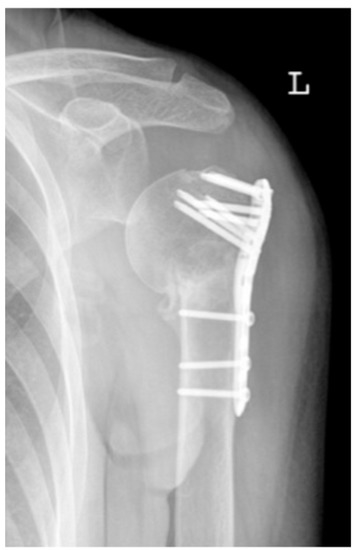

| Complication Type | Exemplary Images by X-rays or Pattern Images | Definition |

|---|---|---|

| 2a | ![]() | Complication Type 2a is defined by varus displacement (<20°) of the humeral head associated with screw cutout through the humeral head cortex. The head sintering is considered relatively stable and non-progressive. |